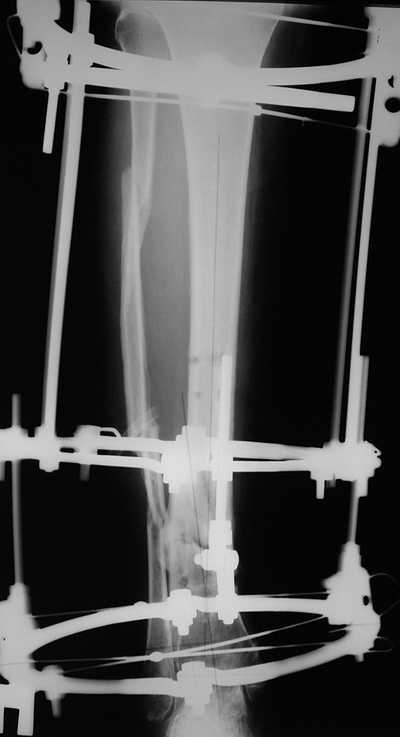

согласно выданной компьютером инструкции. По завершению репозиции

гексаподные телескопы обратно заменены на обычные штанги от аппарата

Илизарова (рис 4 и 5). Еще через две недели забит гвоздь (рис 6, контроль

через 4 месяца).